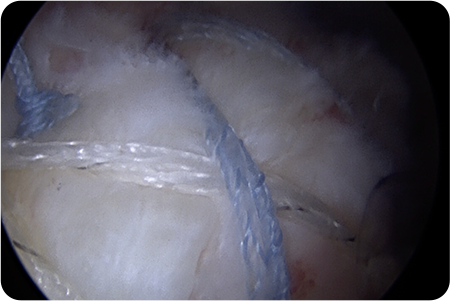

관절경하

회전근개봉합술

관절경을 어깨 관절에 삽입해 파열된 힘줄과

주변 구조를 정밀하게 확인합니다.

견봉하 공간을 넓히고 손상된 부위를 정리한 뒤,

봉합 나사를 이용해 힘줄을 원래 위치에 고정합니다.